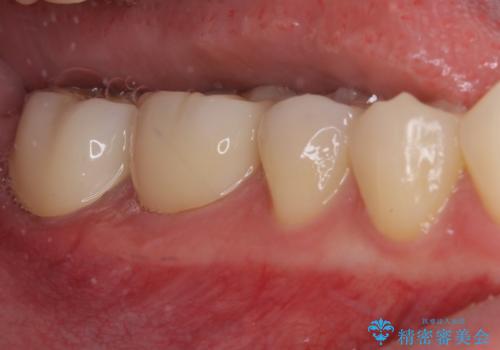

短期間で手間のかからない方法がご希望でしたので、ワイヤー装置による矯正治療を行うこととし、矯正治療後に右奥2歯をセラミッククラウンにて補綴することとしました。

セラミッククラウンによる補綴治療と矯正治療の双方が必要となる場合、矯正治療前の処置や歯の移動中に必要な処置など、二種類の治療を同時にチェックすることがとても重要となります。

当法人では、1つの医院で全ての診療を進めることができるため、このような方には大変お勧めです。